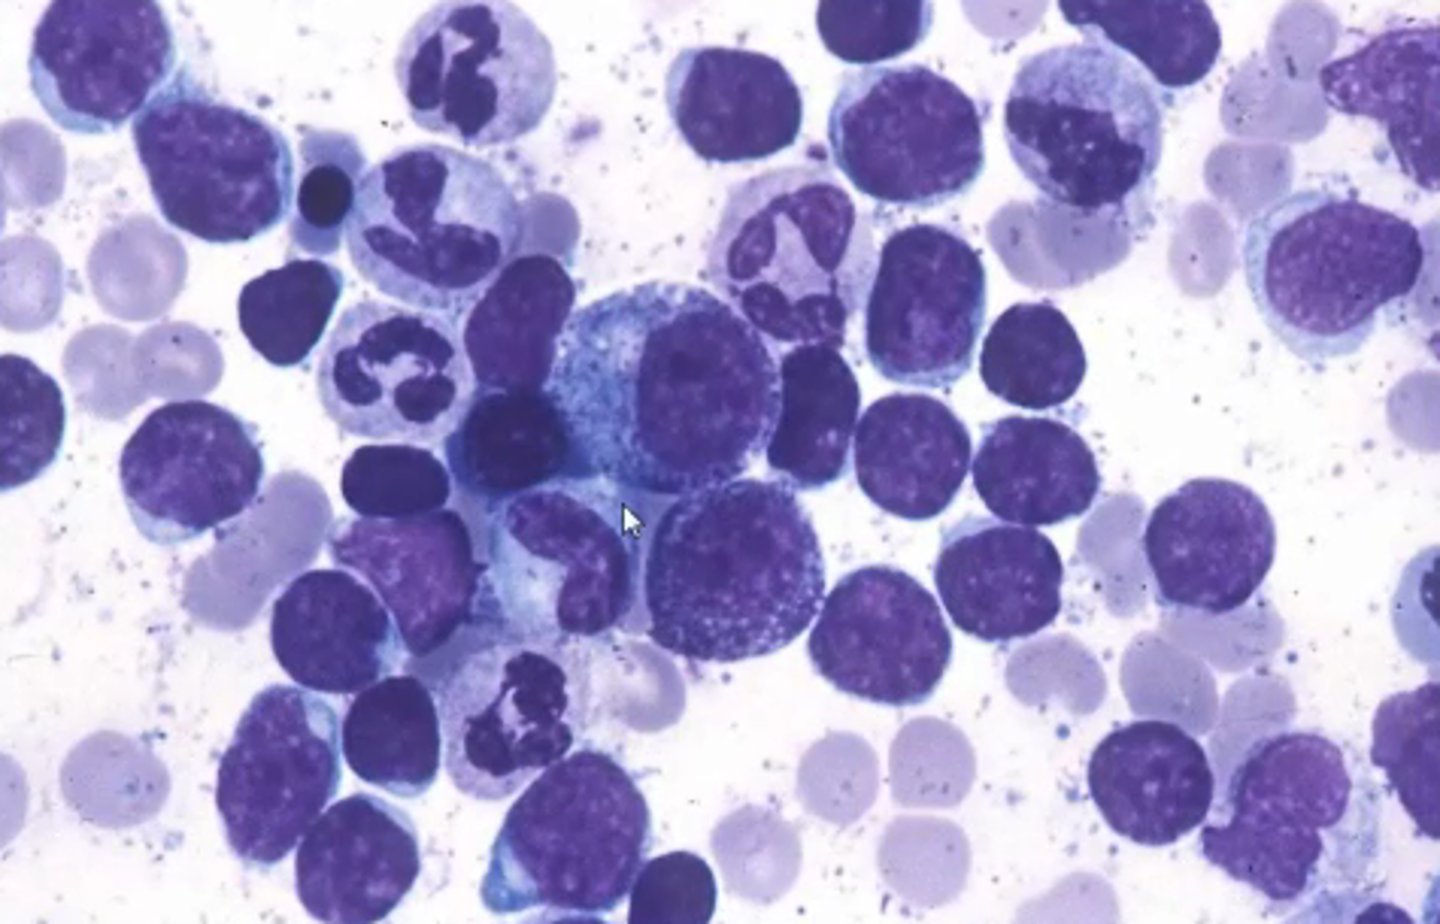

Multiple Myeloma

Definition: Malignancy of plasma cells

Pathogenesis: Terminally differentiated plasma (B) cells secrete a TON of antibodies

Etiology: N/A

S+S: Bone pain, fractures, loss of appetite, weight loss, fatigue, kidney failure

Treatment: Chemo + palliative care :(

Defining characteristics of Multiple Myeloma

High antibody level, osteolytic lesions in bones

What demographic groups are most affected my multiple myeloma?

More common in elderly, men, and African-Americans

How is multiple myeloma detected?

Blood test will detect M proteins (abnormal IgG)

Urine test will detect Bence-Jones proteins (fragment of antibody)